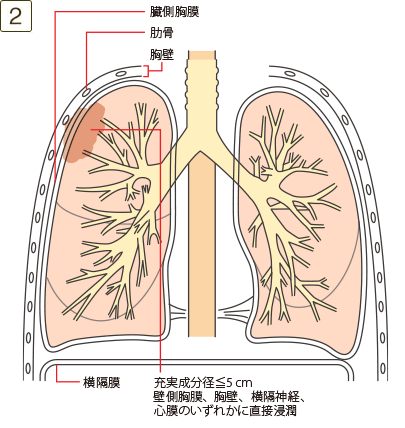

T3

充実成分径>5cmでかつ≦7cm、または充実成分径≦5cmでも以下のいずれかであるもの・壁側胸膜、胸壁(superior sulcus tumor を含む)、横隔神経、心膜のいずれかに直接浸潤・同一葉内の不連続な副腫瘍結節